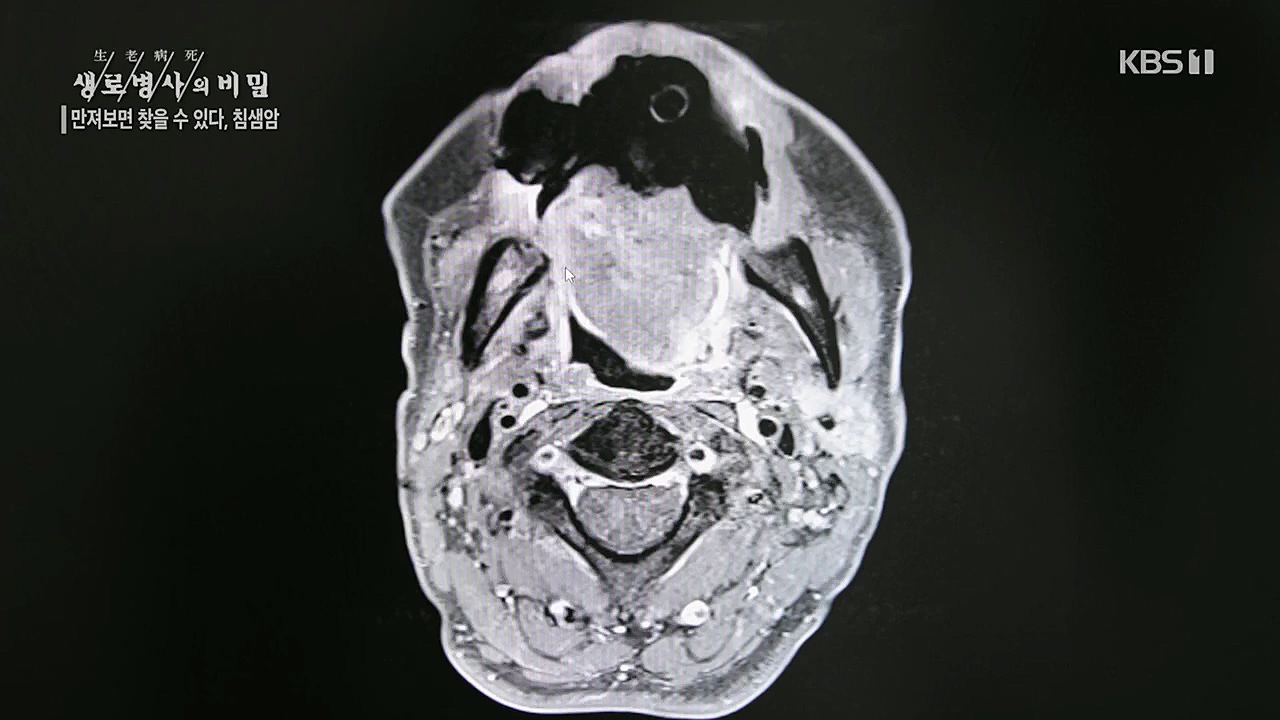

만져보면 찾을 수 있다 침샘암

이게 처음 나왔던 타석입니다

공격적인 암 같은 경우에는 크기가 작고 수술로 완전히 다 제거된다고 하더라도